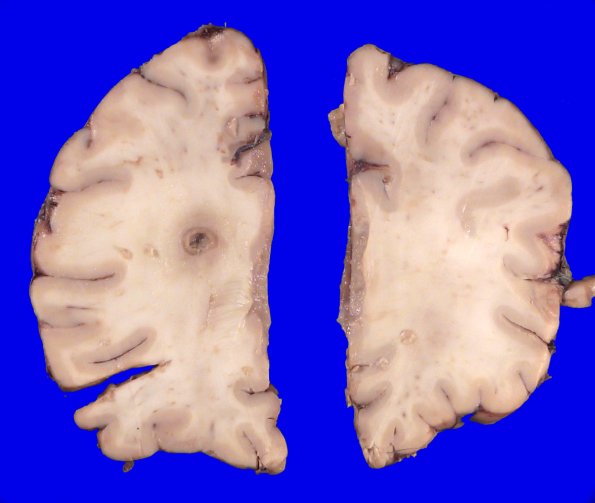

This gross appearance of an abscess shows a developing capsule and perilesional edema.